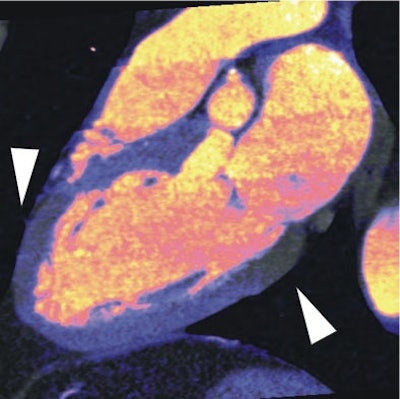

| In a 64-year-old man with chest pain, colored regions of blood-pool images represent iodine, while the darker parts of the myocardium depict ischemia as a lack of contrast uptake. Arrows indicate the myocardial blood-pool deficit, i.e., ischemia. |

SPECT revealed fixed myocardial ischemia in five patients and reversible myocardial ischemia in 11 patients. Dual-source CTA blood-pool imaging correctly identified 90% of the fixed and 88% of the reversible myocardial perfusion deficits seen at SPECT, Schoepf and Ruzsics said.

Compared to SPECT, dual-source CT had 91% sensitivity, 91% specificity, and 91% accuracy for detecting myocardial ischemia by segment, Schoepf said. Compared to coronary catheterization, dual-source CTA had 92% sensitivity, 79% specificity, and 90% accuracy for detecting myocardial ischemia by segment.